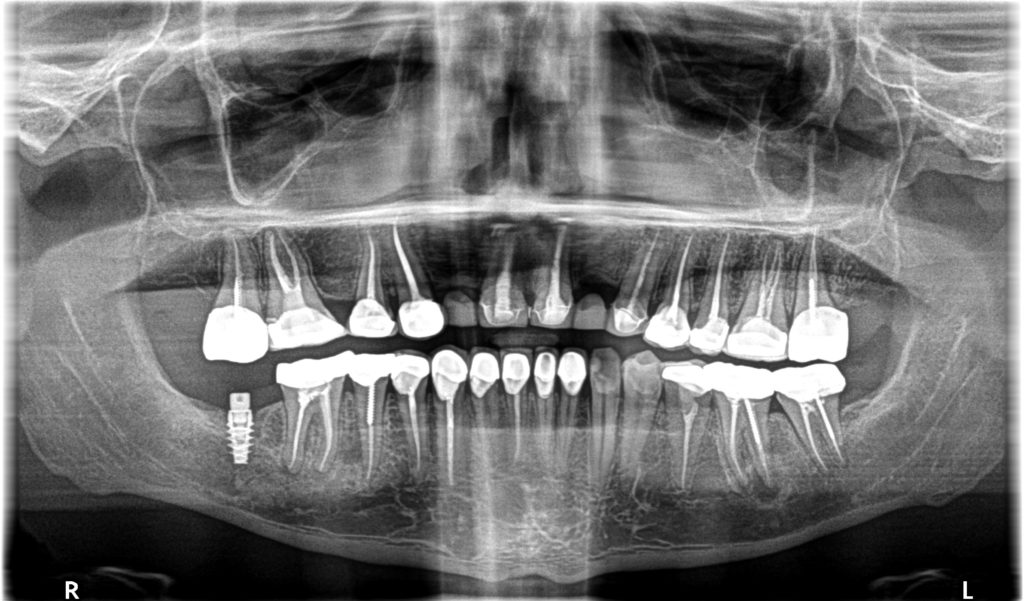

Last week, a patient came in with massive swelling and pain under his crowns. He had traveled to Thailand to have this work done. Yes, had a few fillings to be done, but under general anesthetic, he had been fitted with 24 crowns, 19 Root Canals and 1 dental implant. All billed to his credit card. This is his x-ray. The patient was 31 years of age. Those clinics know that you will leave on a specified date and so everything is rushed, and completed, without giving the body time to assimilate and heal.